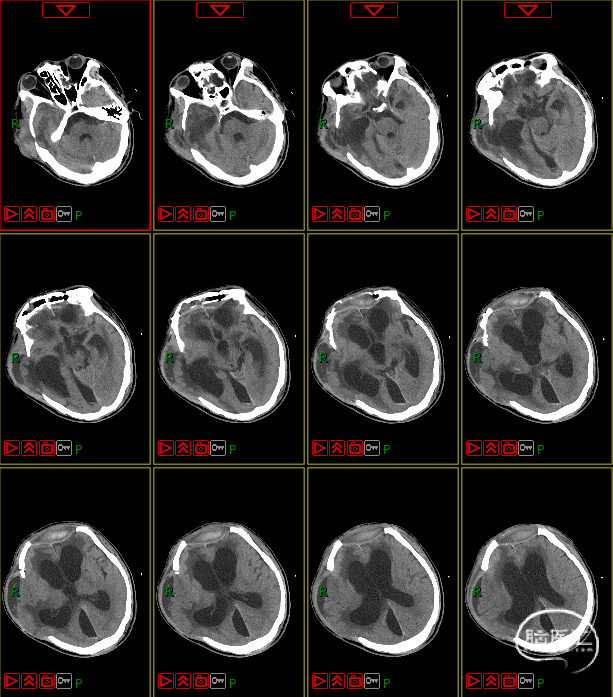

脑积水的处置

第四阶段(多科室康复治疗)

第五阶段(颅骨修补术)

7月16日行PEEK材料颅骨缺损修补术。